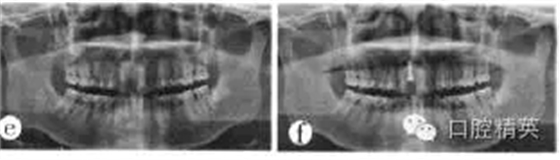

(3)種植修復(fù):拔牙后3個(gè)月行種植修復(fù)。全景片顯示牙槽骨高度及種植空間基本正常(圖1e)。植入1顆3.3 mm×10 mm瑞士ITI種植體;由于唇側(cè)根尖區(qū)骨質(zhì)破壞,致根部種植體暴露約2 mm,取舌側(cè)骨板碎塊充填,嚴(yán)密縫合。術(shù)后x線(xiàn)全景片顯示植體位置、高度等均較理想(圖1f)。種植術(shù)后3個(gè)月行上部修復(fù),全景片顯示植體周?chē)琴|(zhì)致密,骨高度尚可(圖1g)。種植體愈合良好、穩(wěn)固,袖口成形較好(圖1h)。完成種植義齒上部修復(fù)(圖1i)。隨訪(fǎng):種植修復(fù)完成后患者對(duì)咀嚼效率和美觀效果均較滿(mǎn)意?,F(xiàn)已完成種植修復(fù)3年余,修復(fù)體穩(wěn)固,咀嚼效率高,牙齦形態(tài)良好,美觀效果較好。

圖1e種植術(shù)前全景片;f種植術(shù)后全景片;g種植上部修復(fù)前全景片;h牙齦袖口形態(tài);i種植修復(fù)完成